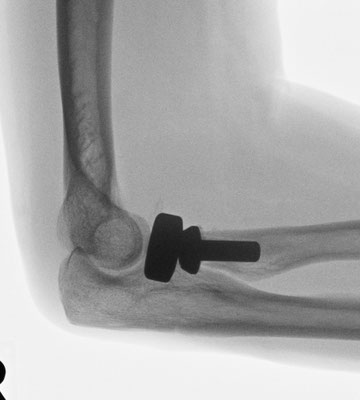

Ellenbogennaher Ellenbruch (Olecranonfraktur)

Der Ellenhaken (Olecranon) stellt den knöchernen Teil dar, über den die Kraft des Trizepsmuskels in den Unterarm geleitet wird und somit die aktive Streckung des Ellenbogens gegen Widerstand ermöglicht wird. Durch den Zug der Trizepssehne wird das kleine Knochenfragment weggezogen. Die Kraftübertragung des Muskels auf den Unterarm ist abgehängt. Insofern ergibt sich die Erfordernis, das Knochenteil und damit auch die Sehne des Trizeps wieder am Unterarm zu befestigen. Zusätzlich muss auch die Kongruenz des Gelenkes wieder hergestellt werden. Je nach dem, ob es sich um einen einfachen oder komplizierten Knochenbruch handelt, wird eine sog. Zuggurtungsosteosynthese mit zwei Drähten und einer Achterschlinge (Abb. 6a-b) oder eine Stabilisierung mit einer Platte durchgeführt.